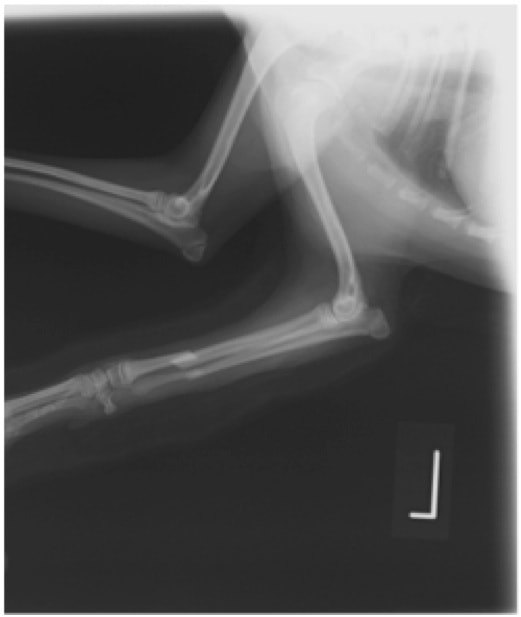

症例:交通事故による椎体脱臼

柴犬:9歳、避妊雌

交通事故直後、胸腰部に激しい疼痛、両後肢に完全麻痺を認め、シェフシェリントン徴候を呈していました。レントゲン検査において、第11-12胸椎間の脱臼が認められました。

脊髄の減圧、脊柱管の再構築・安定化を目的に、片側椎弓切除術およびMatrixMANDIBLE Plateによる椎体固定を実施しました。

隣接椎体を架橋するようにプレートを設置しました。

術後レントゲン写真